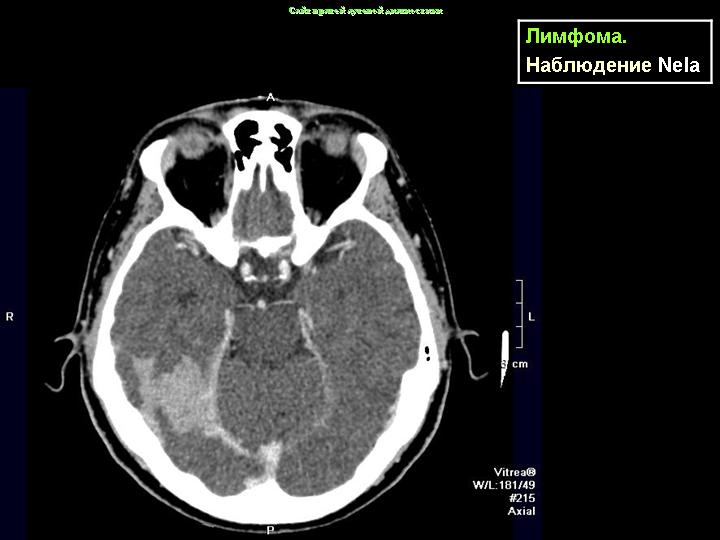

Лимфомы (продолжение набора)

Данные из "интернет-источников".